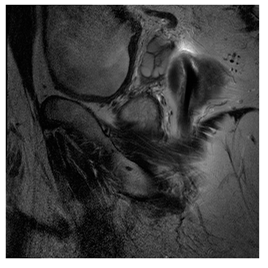

Breast-MRI-NACT-Pilot is an MRI-type image database, collecting breast medical images of 64 patients. Some samples are shown in Figure 12a.

Figure 12.

Sampled images in the tested benchmark databases: (a) Breast-MRI-NACT-Pilot (breast), (b) ACRIN-DSC-MR-Brain (brain), (c) NIH (chest), (d) Lung-PET-CT-Dx (lung), (e) Prostate-MRI (prostate), and (f) Other grayscale standard images.